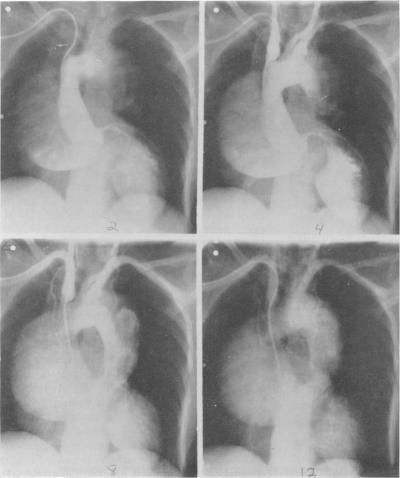

THE SURGICAL TREATMENT OF DISSECTING ANEURYSM OF THE ASCENDING AORTA: WITH A REPORT OF FOUR CASES IN THE CHRONIC STAGE.

Ann Surg. 1964 Jun;159(6):829-45. doi: 10.1097/00000658-196406000-00002.